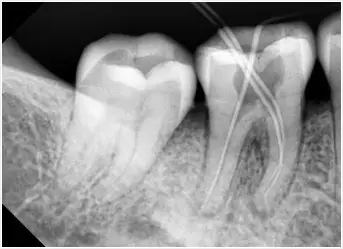

根尖片,隻能看到一兩(liang) 顆牙齒的情況

大家不用有這樣的擔憂,單純的拍x光片檢查牙齒情況花不了多少錢的。目前牙科x光片通常有根尖片(小牙片)、全景片,以及ct片(分小範圍和大範圍),價(jia) 格從(cong) 幾十塊到三四百元左右不等。因此,這些費用是大家都能支付得起的。